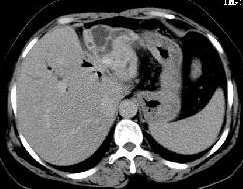

3.B型超聲檢查,膽囊增大,囊壁增厚,可能可看到結石的影像。

膽囊炎應與傳染性肝炎相鑑別,後者肝臟腫大,白細胞數可不增高且有肝功能減退現象。急性膽囊炎、膽管炎伴發腹膜炎時,應與其它原因所致腹膜為如闌尾炎、胰腺炎及消化道穿孔(如傷寒腸穿孔)等症相鑑別。除一般病史、體徵及X線檢查外,超音波可測知膽囊大小及囊壁是事粗糙增厚,腹腔穿刺檢查也有助於診斷。